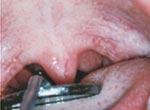

A person with atopy cannot open the

throat wide.

After using Patakara®Lip Trainer it has

been found that the throat is can be opened wide.

Another

effect is that the atopy of the arm has improved to the

level of the photograph below by using it for two months. |